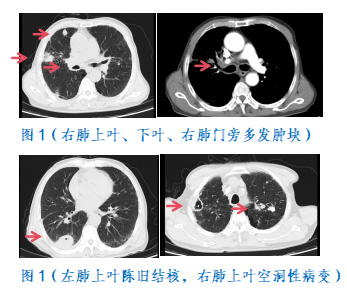

Z先生入住肿瘤科,完善胸部增强CT:“右肺上叶、下叶、右肺门旁多发肿块,左肺上叶陈旧结核,右肺上叶空洞性病变,双肺间质性炎症”(图1)。肺基础差,多种疾病同时共存,出血机制复杂,了解到病情的特殊性,肿瘤科主任胡乃东与肿瘤科介入首席专家陈光利共同讨论,反复评估病情,详细研读增强CT,分析责任病灶及血管分布,设计介入手术路径,详细告知患者家属病情及介入治疗的方式预后,家属愿意介入栓塞止血治疗。